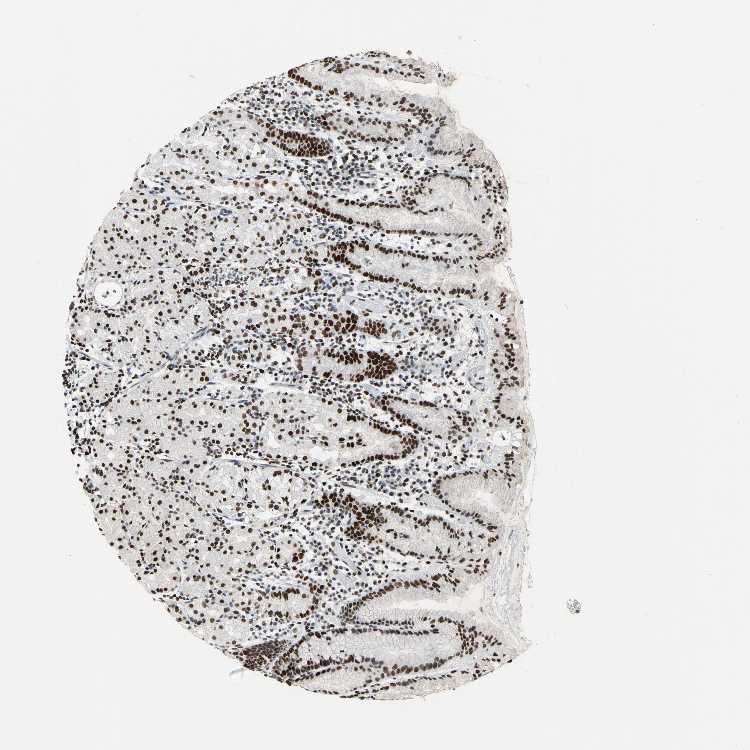

STOMACH 1 - Antibody stainingi

Antibody staining in the annotated cell types in the current human tissue is reported as not detected, low, medium, or high, based on conventional immunohistochemistry profiling in selected tissues. This score is based on the combination of the staining intensity and fraction of stained cells.

Each image is clickable and will lead to virtual microscopy that enables deeper exploration of all samples and also displays staining intensity scores, fraction scores and subcellular localization as well as patient and tissue information for each sample.

Antibody HPA004911

Glandular cells High